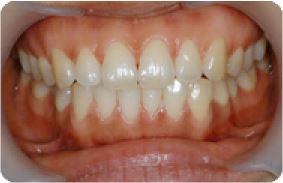

| 9 |

|

임플란트 전후사례 | 2020.03.06 |